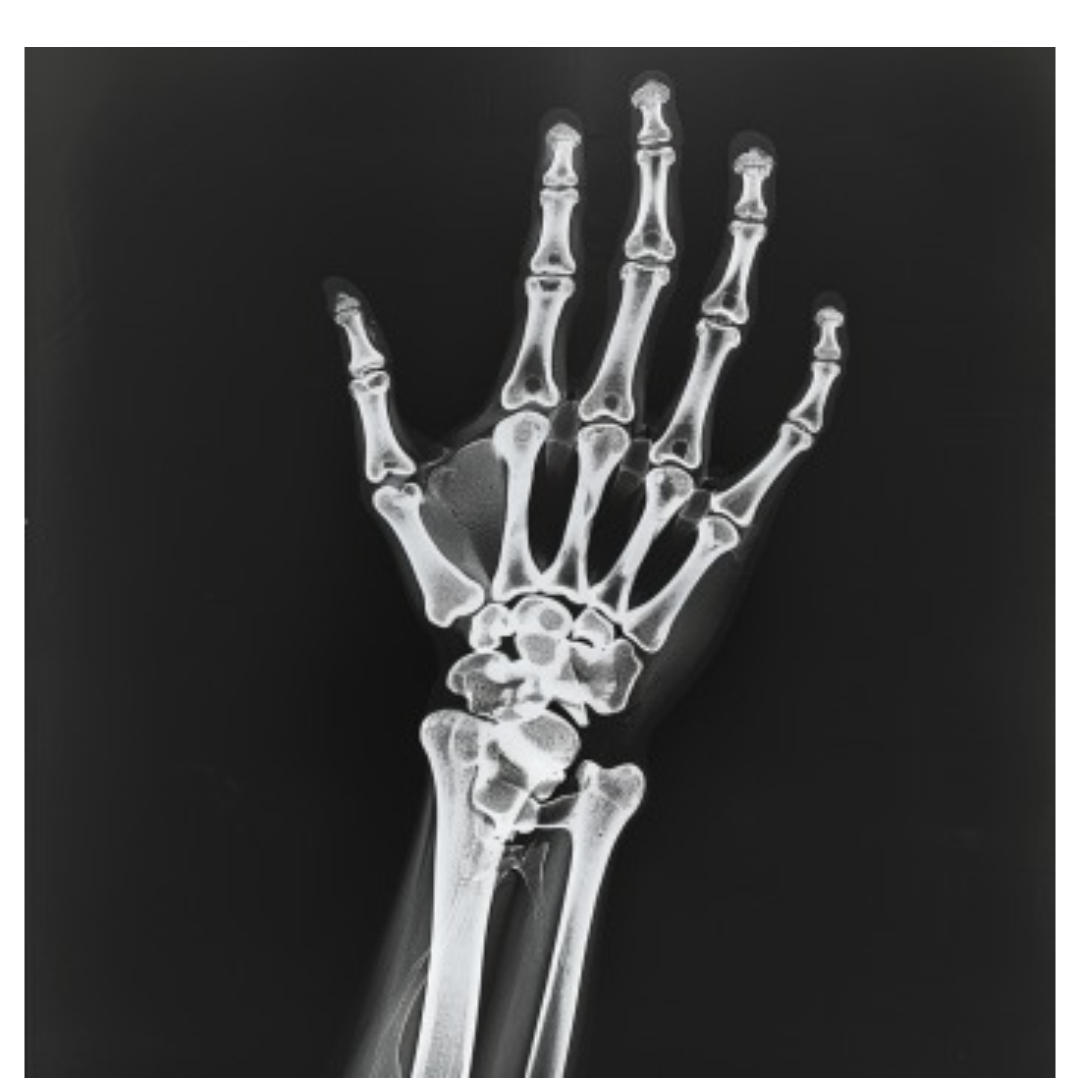

넘어지거나 충격을 받을 때 손목을 보호하려다 손목이 골절되는 경우가 있습니다. 손목 골절은 고통스럽고, 손목이 붓고 움직이지 않을 수 있습니다.

골절이 의심된다면 즉각적으로 병원을 방문해 X-ray 검사를 통해 진단을 받아야 하며, 석고 고정이나 수술이 필요할 수 있습니다. 재활 치료도 필수적입니다.